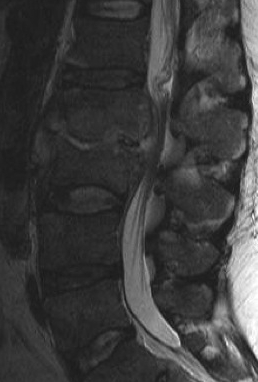

Xray / MRI

MRI with Gadolinium

Investigation of choice

- well vascularized inflammatory tissue enhances on T1

Osteomyelitis changes include

- confluent hypointensity of involved bodies on T1

- hyperintensity of involved bone and disc on T2

- loss of distinction of involved bone & disc

- abnormal disc appearance